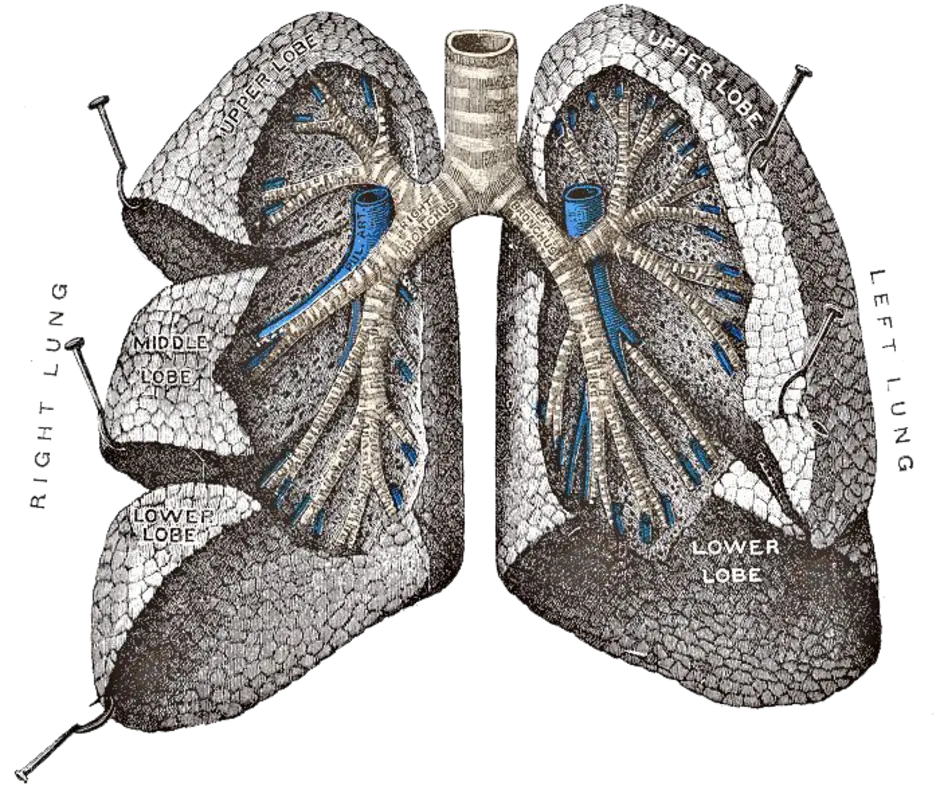

Анатомические изображения сегментов легких различных животных

Раздел: Другие животные